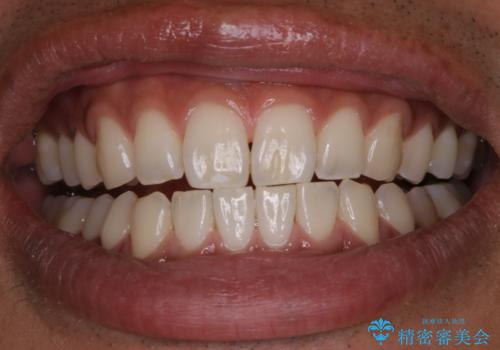

PMTCで清潔感のある明るい口元に

PMTCを行うことで、ご自身本来の歯の色になり自然な明るさになります。

口元が自然な明るさになることで、より清潔感のある印象になるため結婚式・行事やイベント前などにもPMTCを行うはおすすめです。